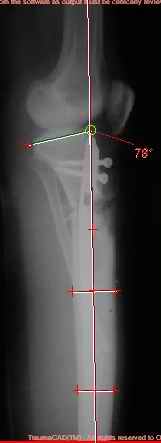

Продолжение обсуждения, начатого в октябре прошлого года (см. здесь) Наконец-то оперировали эту пациентку. Биопсию сделали - опухолевого ничего нет. Пока все участвовавшие в обследовании смежные специалисты и ортопеды сошлись, что это молокальная монооссальная фиброзная дисплазия. 20 марта наложили аппарат, сделали чрескожную остеотомию. К 3 апреля все докрутили. Сегодня заштифтовали. Начальные и итоговые снимки в приложении. Рекурвацию можно было еще немного больше устранить, и чуть кзади сместить диафиз. Но вроде и так ничего выглядит, по сравнению с тем, что было. Комментарии приветствуются.

ничего не понимаю в детской и ортопедии, но в боковой проекции нет рекурвации,

а даже немного гиперкоррекция, что по-моему есть хорошо. Кортикалы по задней стенке совпадают, диафиз на одну неправду кзади.